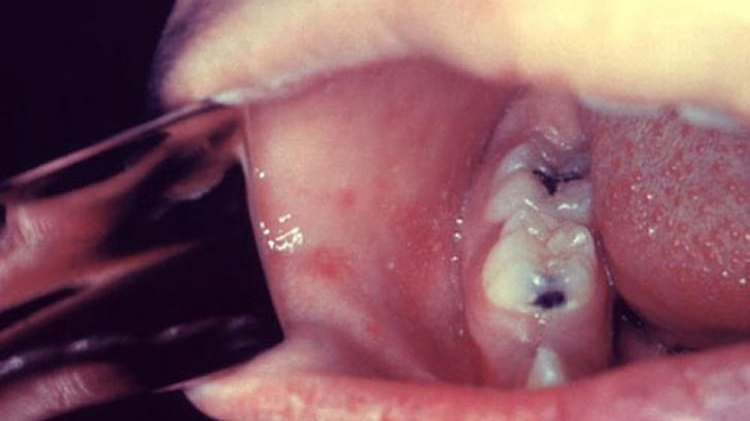

– Giai đoạn khởi phát (giai đoạn viêm long): trong 2 – 4 ngày. Trong giai đoạn nàyngười bệnh sốt cao, viêm long đường hô hấp trên (ho, chảy mũi) và viêm kết mạc. Có thể thấy hạt Koplik là các hạt nhỏ có kích thước 0,5 – 1 mm màu trắng/xám có quầng ban đỏ nổi gồ lên trên bề mặt niêm mạc má (phía trong miệng, ngang răng hàm trên). Hạt Koplik thường xuất hiện một ngày trước phát ban và tồn tại 2 – 3 ngàysau khi ban xuất hiện;